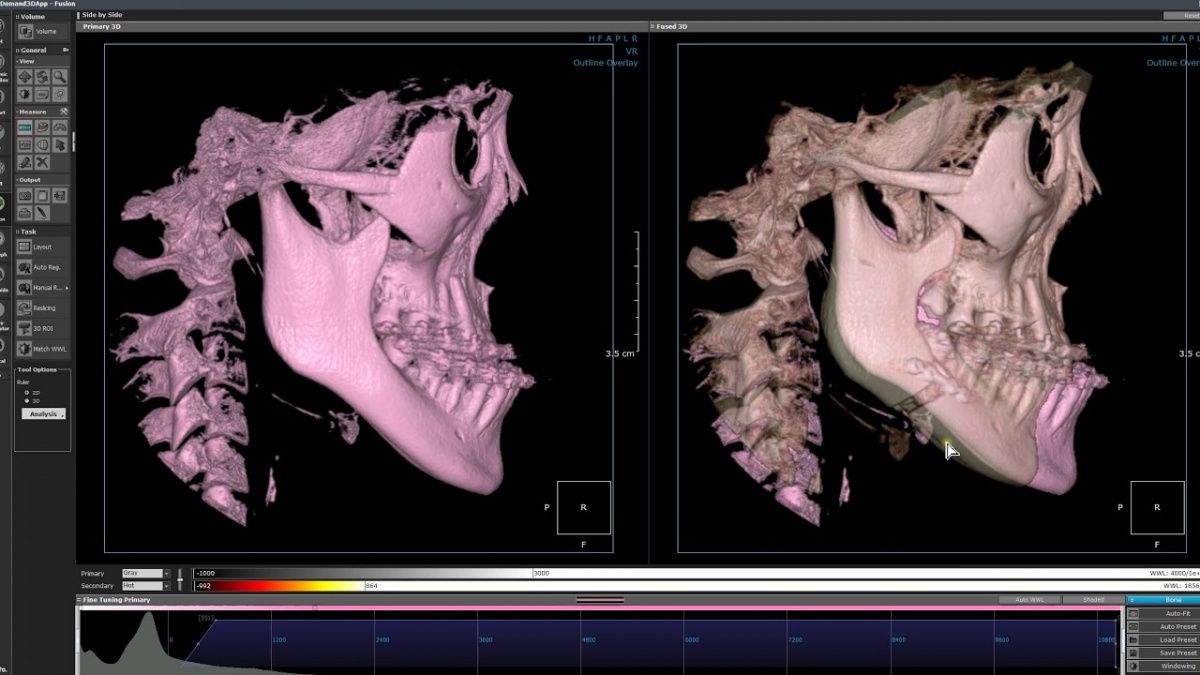

Немаловажным, а может главным вопросом, является универсальность программы-просмотровщика, в которой будут работать врачи-стоматологи. У Papaya 3D есть два варианта программ: Triana и OnDemand3D. Оба просмотровщика обладают схожим интерфейсом и имеют самые важные опции, а именно:

Triana.jpg  OnDemand3D.jpg

• режим MPR (многоплоскостная реконструкция). Именно здесь выстраивается интересующий участок челюсти или зуба для анализа.

• панорамный реформат. Возможность постройки классической и сегментарной панорамы позволяет продемонстрировать план лечения пациенту, а также оценить расположение анатомических структур на боковых кросс-секциях.

• модуль дентальной имплантации. Возможность виртуальной установки дентального имплантата с анализом окружающей костной ткани. В библиотеке представлен широкий спектр имплантологических систем с индивидуальной прорисовкой имплантата.

• выделение нижнечелюстного канала позволяет продемонстрировать расположение важного анатомического образования и определить зону безопасности при проведении лечения.

• функции плотности, линейных измерений и угла – необходимы для получения полноценной информации для последующего лечения.

• 3D режим – показывает трехмерную модель челюсти с целью определения аномалий, деформация, а также визуализации виртуальных имплантатов.

triana3.jpg triana4.jpg triana5.jpg

OnDemand3D (1).jpg OnDemand3D (2).jpg OnDemand3D 1.jpg

Таким образом обе программы являются простыми в пользовании, но обладающими обширным спектром возможностей для диагностики любыми специалистами-стоматологами. В данные программы происходит загрузка классических файлов DICOM 3.0, которые являются общепринятым форматом записи данных пациента. Это важный момент, так как позволяют врачу, имеющему полную версию программы загружать даже сторонние исследования и просматривать их в этих программах. Простота в освоении этих программ позволяет даже специалисту, не работающему раннее с этими программами, быстро адаптироваться и получить качественную информацию. Возможность выгрузки STL-файла дополнительно создает возможность интегрировать данные с цифровым ортопедическим протоколом.